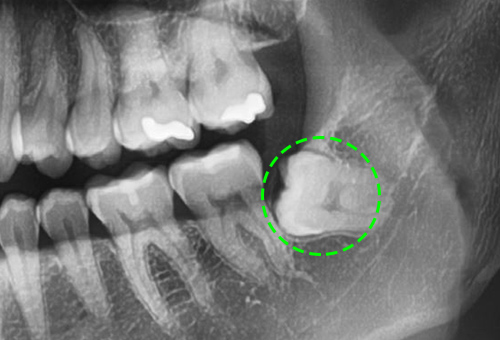

• 기울어진 사랑니

사랑니 바로 앞 어금니를 간섭해, 충치가 발생할 확률이 매우 높고 이로 인해 치열이 불규칙해 질 수 있습니다.